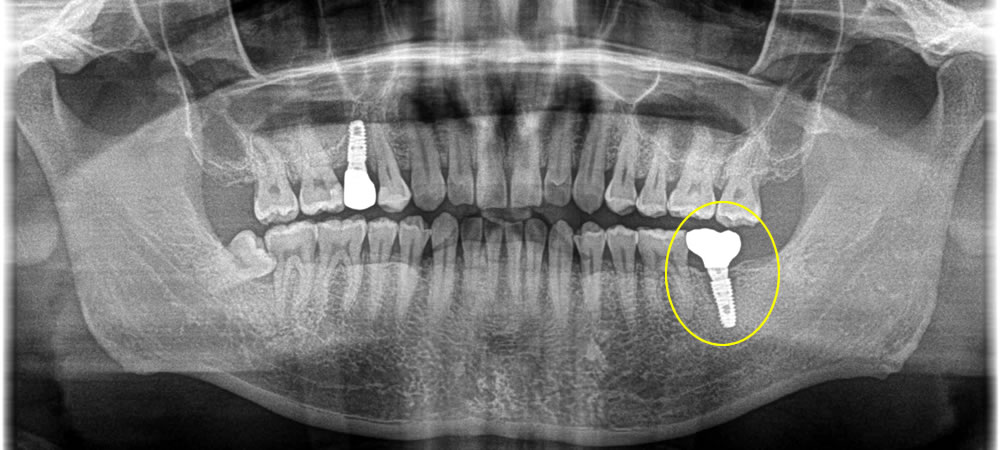

破折したインプラントを取り除いて再治療した症例

年齢

40代

性別

男性